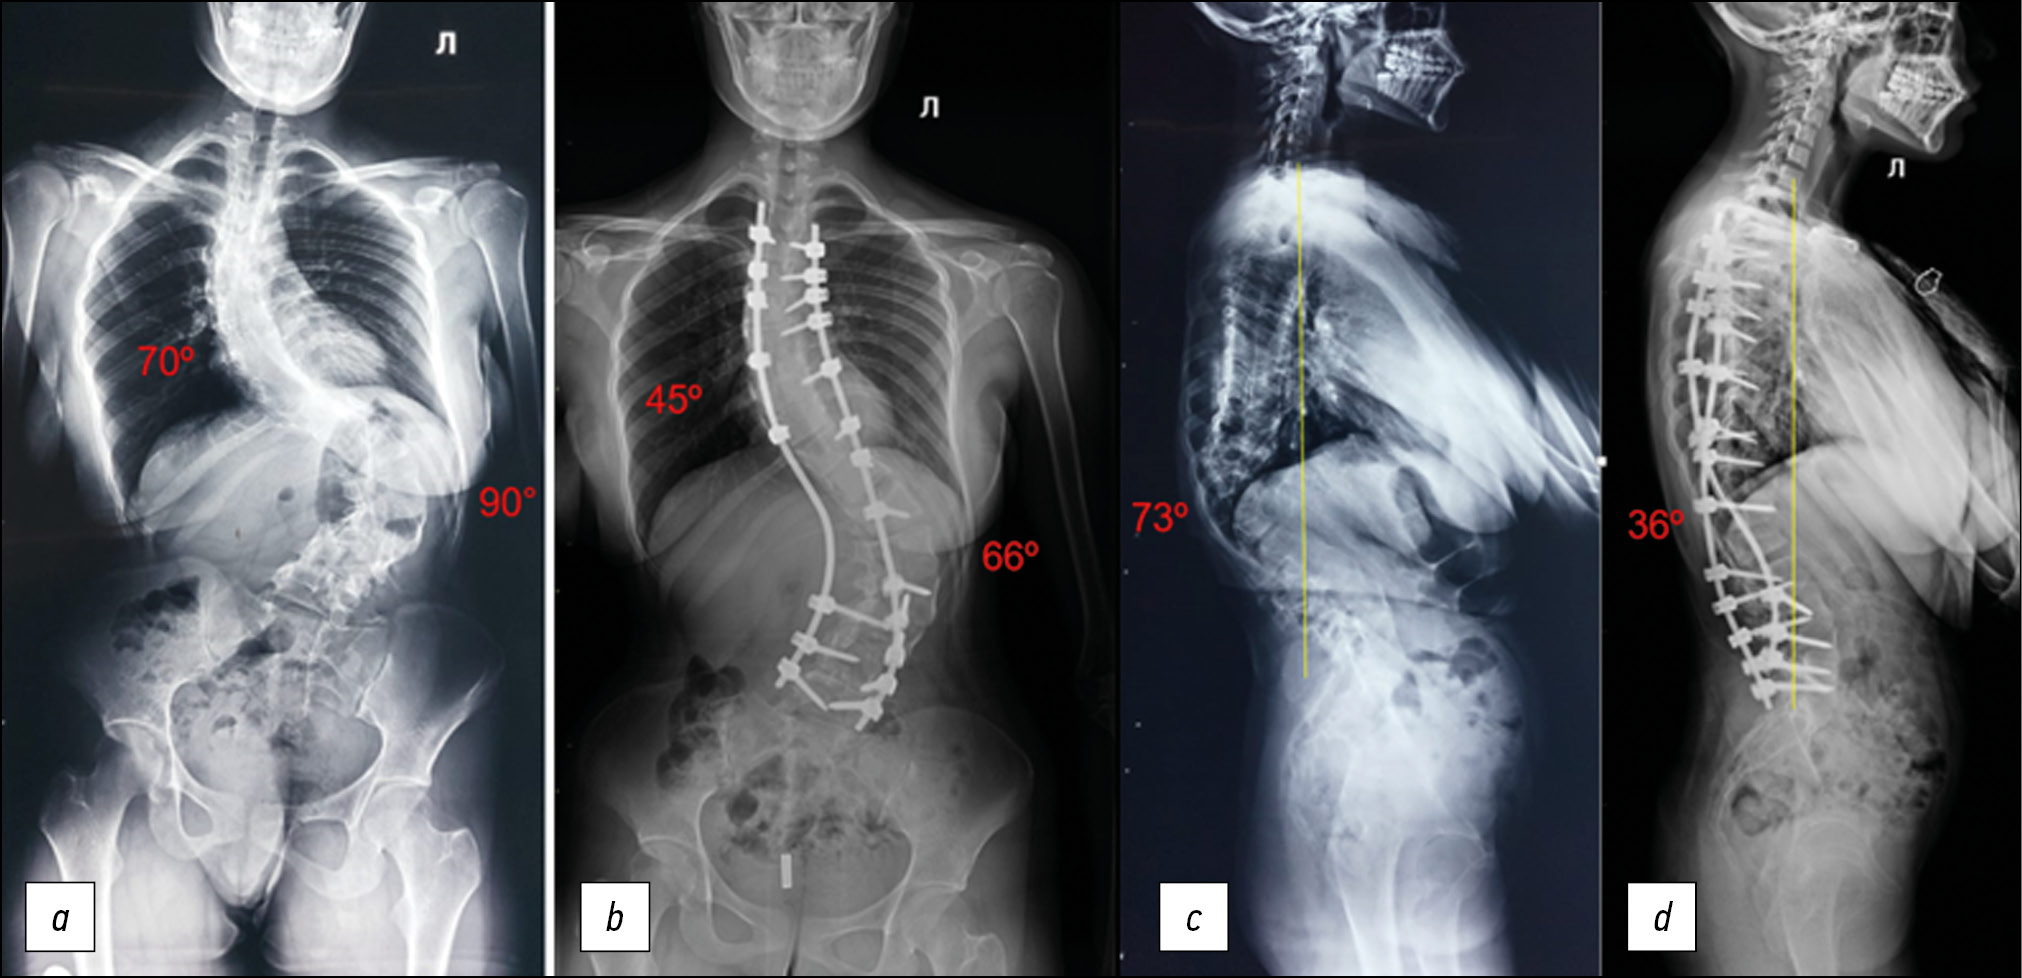

Postural spondylograms revealed left-sided thoracolumbar degree IV kyphoscoliosis, with a scoliotic deformity angle of 70° in the thoracic region, 90° in the lumbar region, local kyphosis angle of 73° in the thoracolumbar transition, and 5.7 cm of negative sagittal imbalance (SVA, sagittal vertical axis) (Fig. 1).

Fig. 1. Postural spondylograms upon admission.

The surgery was carried out with 6 kg of intraoperative halo-traction and intraoperative neuromonitoring. A posterior median incision was used to gain access to the surgical area. At the ТIII–LV level, the spine was corrected and stabilized with metal structures, and posterior spinal fusion with autogenous bone was performed. The total amount of blood lost was 1100 ml. The postoperative wound was healed by primary intention. On the control postural spondylograms, there was a satisfactory correction of scoliotic deformity of the thoracic region (45°), lumbar spine (66°), and local kyphosis at the level of the thoracolumbar transition (36°); the sagittal balance of the spine was significantly improved, the imbalance was leveled, SVA = 0 cm (Fig. 6). The visual improvement in the back profile was also recorded (Fig. 7).

Fig. 6. Postural spondylograms in 2 projections (a, b) before surgery and (c, d) after.